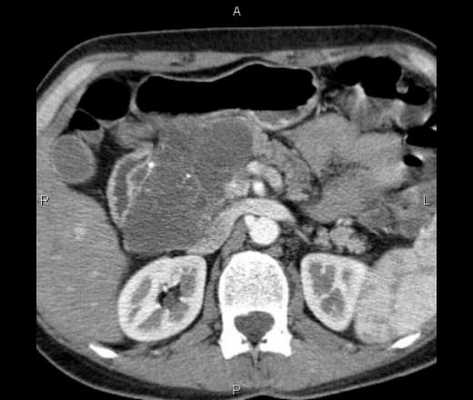

Инфаркт сальника имитирущий аппендицит

По данным публикации в Международном журнале Хирургических случаев (International Journal of Surgery Case Reports) за апрель 2019 - Idiopathic segmental infarction of the omentum mimicking acute appendicitis: A case report / Идиопатический сегментарный инфаркт сальника, имитирующий острый аппендицит: клиническое наблюдение - внешняя ссылка

26-летний мужчина с жалобами на острую боль в правой подвздошной области, связанную с тошнотой и рвотой в течение 4 дней. При клиническом осмотре присутствовало напряжение в правой подвздошной области. Исследования крови были в пределах нормы. УЗИ показало наличие небольшого количества свободной жидкости в правой подвздошной области. Червеобразный отросток не был визуализирован. На контрастно-усиленной компьютерной томографии брюшной полости и малого таза отмечалось наличие свободной жидкости в правой подвздошной области с утолщением правой латероканальной фасции и скоплением сальникового жира. Просвет аппендикса был пустой, а верхушка аппендикса утолщенной. На основании этих результатов был поставлен клинический диагноз острого аппендицита, и пациенту была запланирована лапароскопическая аппендэктомия.

Инфаркт сальника редко встречается в клинической практике из-за его богатой васкуляризации. Однако, если это происходит, то он может быть как первичным, так и вторичным. В большинстве случаев он является вторичным по отношению к идентифицируемой причине, такой как сдавленная паховая или вентральная грыжа, сосудистый тромбоз, новообразования и воспалительные состояния. Первичный инфаркт сальника встречается редко, в литературе сообщается о 400 случаях. Ожирение является важным фактором риска развития сальникового инфаркта. Он может быть сегментарным или включать весь сальник. Правая сторона сальника является наиболее часто поражаемой частью сальника, как в настоящем случае. Вероятная причина преобладания правой стороны заключается в том, что сальник на правой стороне имеет большую длину и большую подвижность, по сравнению с левой стороной.

Традиционно первичный идиопатический инфаркт сальника подлежит хирургическому удалению. Но с увеличением числа случаев, диагностируемых по радиологическим изображениям, было установлено, что это самоограничивающееся заболевание, и в большинстве случаев его можно лечить медикаментозной терапией. Однако может быть реадмиссия(*т.е операция) при рецидивирующей или продолжающейся боли в 25% случаев. Кроме того, у некоторых пациентов на медикаментозной терапии может развиться сальниковый абсцесс, требующий хирургического вмешательства. Лапароскопическое иссечение является процедурой выбора в случае неудачи медикаментозного лечения и в тех случаях, когда предварительная операция выполняется из-за диагностической дилеммы, как это видно в данном случае.

Идиопатический сальниковый инфаркт является редкой причиной болей в животе у молодых людей. Он должен быть включен в дифференциальные диагнозы при лечении пациентов с острым животом.

*Также в публикации присутствуют снимки КТ и интраоперационный снимок.